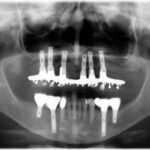

Antes de empezar con el tratamiento implantológico se realiza un estudio radiológico mediante radiografías intraorales, ortopantomografía y CBCT (tomografía computerizada de haz cónico).

Sí, para valorar el área a tratar con implantes es muy importante realizar radiología 3D y así estudiar la cantidad y calidad del hueso donde se colocarán los implantes. También es importante para estudiar el estado de los dientes vecinos.

Es por ello que en una primera visita se realiza ortopantomografía y radiografías intraorales para valorar el estado de salud oral del paciente, pero cuando se va a necesitar un tratamiento implantológico siempre se debe realizar un CBCT.